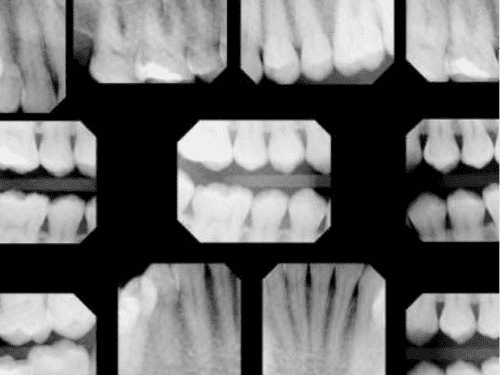

Digital X-Rays

Modern digital dental x-rays benefit patients in a number of ways:

• Digital x-rays expose patients to considerably less radiation than conventional film x-rays.

• Digital x-rays require almost no time for development, reducing time spent waiting in the dental chair.

• Digital x-rays allow for incredibly precise and accurate images for timely diagnoses.

• Digital x-rays are securely stored in your digital file and can be securely sent to your insurance company or specialists, when necessary.

Because no chemicals are needed for developing and no space is needed for film storage, digital x-rays are better for the environment.